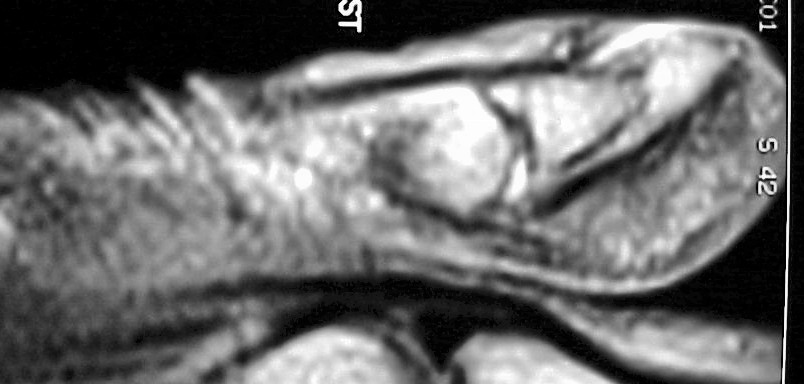

MRI demonstrated ill defined soft tissue replacement of the majority of the distal phalanx:

With contrast enhancement of the transformed area: